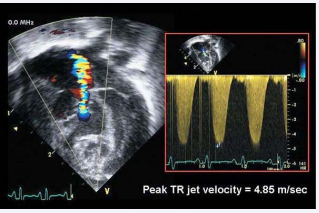

PULMONARY SYSTOLIC PRESSURE/RVSP

TR velocity peak permits estimation of RVSP with the addition of RA pressure, assuming no significant RVOT obstruction. It is advised to use the RA pressure estimated from IVC and its collapsibility, rather than arbitrarily assigning a fixed RA pressure. TR velocity > 2.8 to 2.9 m/s, corresponding to SPAP of approximately 36mm Hg, assuming an RA pressure of 3 to 5mmHg, indicates elevated RV systolic and PA pressure (Figure 9).

Figure 9: Measure of systolic pulmonary artery pressure.